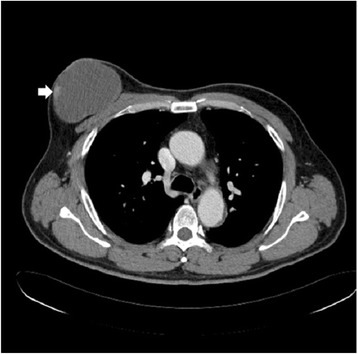

A 53-year-old Korean man presented to our hospital with a painful, large, round chest wall mass beneath the right nipple measuring about 10 × 10 cm in size. The skin overlying the mass was reddish and hyper-pigmented. The mass had been present for more than 8 years but had grown rapidly over the past few months. There were no palpable lymph nodes and no other breast masses on physical exams. A chest CT showed no remarkable lymph nodes and a 9.3 × 6.7 cm, well-defined, thin-walled, cystic mass with some nodular enhancing lesions in the lateral wall of the mass. This suggested a benign soft tissue mass, such as a large epidermal inclusion cyst (Fig. 1). Because we considered the mass to be a benign cystic mass, we excised it without lymph node dissection. We were able to save the nipple because the mass was limited to the subcutaneous layer beneath the areolar tissue. The mass was a well-encapsulated cystic lesion that contained old blood material, and there was no gross invasion into the surrounding tissue. Microscopic examination revealed an intracystic papillary projection (focal area with papillary projection), representing in situ carcinomatous lesions with apocrine features. A microscopic focus of the invasive carcinoma was identified in the cystic wall adjacent to the in situ lesions (Fig. 2a). Tumor cells had abundant eosinophilic cytoplasm and vesicular hyperchromatic nuclei with focal decapitation secretion (Fig. 2b). Most tumor cells were located within the in situ lesions and in the papillary projections, and the tumor tissue focally invaded the cystic wall adjacent to the papillary projections. However, the tumor had not invaded the surrounding tissue, such as subcutaneous tissue, muscle, or dermis (Fig. 2). Serial sections of the whole resected specimen failed to show breast parenchymal tissues. Immunohistochemical study showed that the tumor cells were positive for cytokeratin AE1/AE3, gross cystic disease fluid protein (GCDFP)-15 (Fig. 3a, b), and estrogen and progesterone receptors (Fig. 3c, d). Based on these findings, the preliminary pathological diagnosis was carcinoma with apocrine features. Clinical evaluations, including positron emission tomography-computed tomography (PET-CT), chest CT, abdominal and pelvic CT, colonoscopy, and duodenoscopy, were performed in order to exclude other potential primary malignancies, and no other potential primary malignancy was identified. Based on these characteristic features, we diagnosed the tumor as primary cutaneous apocrine gland carcinoma (cribriform and cystic form). The postoperative course was uneventful, and at present, 36 months after the surgery, no recurrence or metastasis has been identified, and the patient has not received any adjuvant therapy.

Fig. 1.

Chest CT shows a 9.3 × 6.7 cm, well-defined, thin-walled cystic mass in the right subareolar region with nodular enhancing lesions in the lateral wall, suggesting a benign soft tissue mass such as a large epidermal inclusion cyst